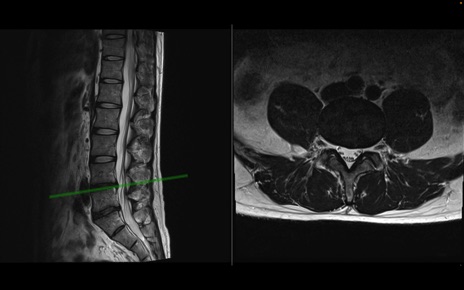

【症例】40歳代男性

【主訴】左臀部〜大腿後面痛み

【現病歴】2週間前から腰痛あり。2日前に夜中にくしゃみをした際に激痛が出現。疼痛強いため来院。

【身体所見】左臀部〜大腿後面、下腿後面のしびれ。SLR -/+ 30度、うつ伏せ困難、筋力低下なし。

異常所見と診断は?